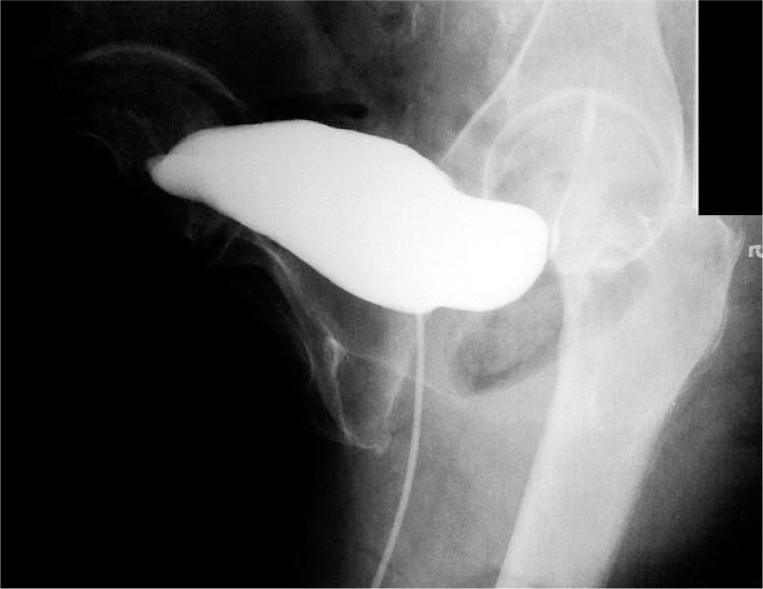

Some minimally invasive techniques have been introduced to decrease morbidity related to standard laparoscopic procedures. One such approach is laparoendoscopic single-site surgery (LESS), which can also be applied for transvesical surgery. The aim of the study was to present our initial clinical experience of using this technique for transvesical vesicovaginal fistula (VVF) repair. In August 2011, we carried out the LESS repair of a 3-mm in diameter vesicovaginal fistula on a 72-year-old woman, who failed the conservative treatment with Foley placement. The procedure was performed transvesically (percutaneous intraluminal approach) with a single-port device (4-channel, TriPort+, Olympus Winter&IBE GMBH) via a 1.5-cm incision made 2 cm above the pubic symphysis. A standard 10-mm optic and straight laparoscopic instruments were used. The fistulous tract was dissected and partially excised. The bladder and vaginal wall defects were closed in two layers with running absorbable V-Loc (Covidien, Norwalk, CT, USA) suture. Ureteral catheters were left for 5 days and the Foley catheter for 14 days. The operative time was 170 min. The blood loss was minimal. No complications were observed. The postoperative period was uneventful. During a 6-month follow-up the patient reported no involuntary discharge of urine into the vagina. Diagnostic scans revealed no presence of VVF and laboratory examination results were all within the normal range. Although substantial development of the instruments and skills is needed, the transvesical LESS vesicovaginal fistula repair appeared to be feasible and safe. Nevertheless, further experience and observations are necessary.

一些微创技术已被引入以降低与标准腹腔镜手术相关的发病率。其中一种方法是经自然腔道内镜手术(LESS),其也可应用于经膀胱手术。本研究的目的是介绍我们使用该技术进行经膀胱膀胱阴道瘘(VVF)修复的初步临床经验。2011年8月,我们对一名72岁女性进行了直径3毫米膀胱阴道瘘的LESS修复,该患者经放置Foley导管的保守治疗失败。手术经膀胱(经皮腔内入路),通过耻骨联合上方2厘米处1.5厘米的切口,使用单孔装置(四通道,TriPort +,奥林巴斯Winter&IBE有限公司)进行。使用标准的10毫米光学镜头和直腹腔镜器械。分离并部分切除瘘管。膀胱和阴道壁缺损用可吸收的V-Loc(美国科惠力公司,诺沃克,康涅狄格州)连续缝合分两层关闭。输尿管导管留置5天,Foley导管留置14天。手术时间为170分钟。失血极少。未观察到并发症。术后过程顺利。在6个月的随访中,患者报告无尿液不自主排入阴道。诊断性扫描显示无膀胱阴道瘘,实验室检查结果均在正常范围内。尽管需要仪器和技术有实质性的发展,但经膀胱LESS膀胱阴道瘘修复似乎是可行和安全的。然而,仍需要进一步的经验和观察。